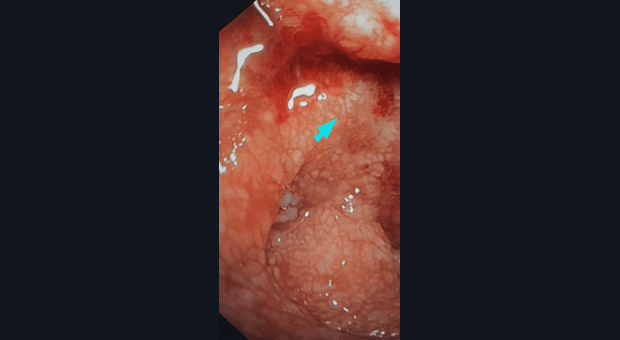

Девушка 1985 года рождения, в анамнезе роды 5 месяцев назад, лактация. ЛХЭ в 2015г. Жалобы на дискомфорт в эпигастрии, вздутие, не температурит. Данное образование в области верхнего дуоденального изгиба, выполнена биопсия, при взятии биопсии, из центра образования, выделилось мутное содержимое в скудном количестве (гной?). Коллеги, ваше мнение. Спасибо.